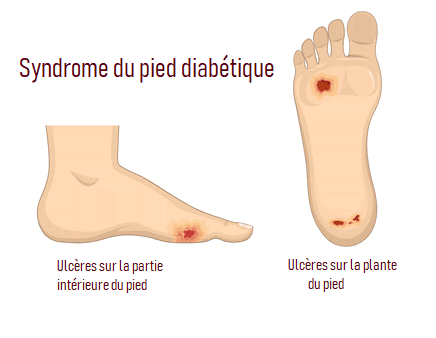

La première branche est centrée sur les problèmes unguéaux et cutanés: les ongles incarnés, les mycoses, les verrues, le suivi des personnes diabétiques (contrôle de la sensibilité, de la mobilité, de la peau et des ongles), la modification de la position des orteils grâce à la confection d’orthoplasties (orthèses en silicone réalisées sur mesure), la modification de la courbure des ongles via la mise en place d’orthonyxies (bridges de l’ongle permettant de le redresser et de supprimer les conflits.)

- Soins/contrôle pour diabétiques